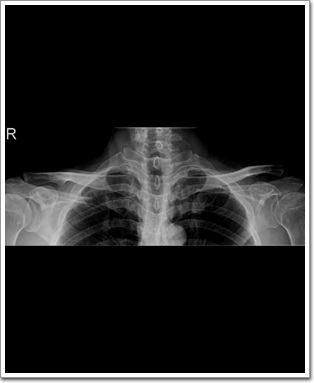

Clavicle AP

Purpose

Clavicle Fracture, Congenital Deformity, A-C JointDislocation 상태를 진단할 수 있다.

Position

환자는 Supine 또는 Erect Position을 취한다.

Coracoid Process의 높이에 견부의 외측연과 구간부의 정중면 사이 중앙에 Detector의 중앙이 오도록 한다.

Check Point

Clavicle 전체가 포함되어야 한다.